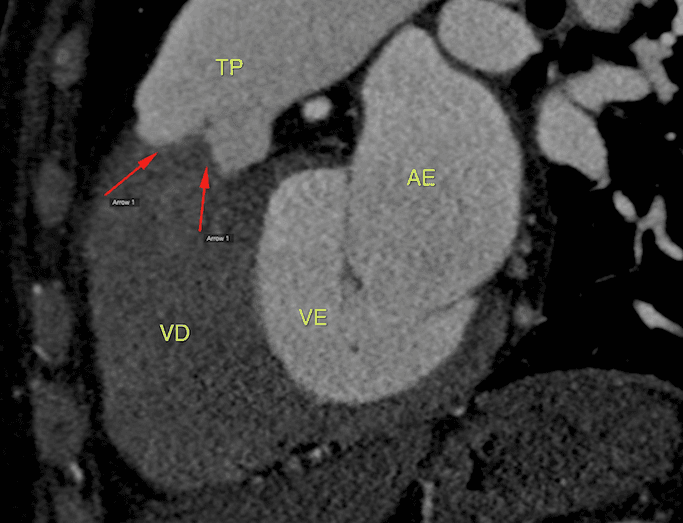

María de 57 años, en una evaluación pre-operatoria de cambio de válvula aórtica por insuficiencia importante. Sometida a cineangiocoronariografía incompleta por no ser posible la cateterización de la …

1 MARÇO 2019